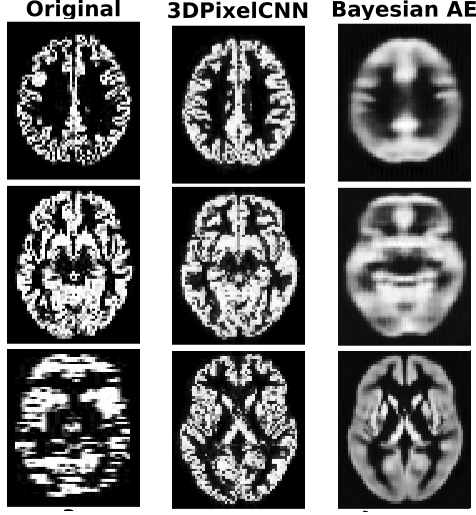

Figure 2 shows a representative selection of reconstructions of GM volumes and unsupervised lesion masks produced using . Notice on the MRI reconstruction, when the original image is corrupted, the 3DPixelCNN model acts as a super resolution mechanism, further showing the model has learnt and is not simply memorising the training set.

For semantic segmentation using , the increase is most noticeable at smaller with an improvement of 0.082 (25.6%) in Dice coefficient for and an average increase of 0.056 (15.2%) for all . Using provides less of a performance gain, with an average increase in Dice of 0.025 (6.9%). For age regression and sex classification, we notice a steady increase in performance when using , with an average error reduction of 0.30 years (3.98%) and accuracy increase of 1.87%, respectively. Using , on the other hand, results in an average error reduction of 0.68 years (9.09%) for age regression and accuracy increase of 3.36%, for sex classification. Using the Bayesian AE’s results in a performance degradation of at least 2% for all tasks, compared to using the original volume. We suspect this is because here is relatively noisy, as can be seen in Fig. 2. On the other hand, using the latent space, , results in an average 5.6% increase for the age regression task and a 2.2% increase for sex classification. The Bayesian AE’s latent space degraded performance for the semantic segmentation task.

Clearly, 3DPixelCNN’s uncertainty measures help most with semantic segmentation. They seem to be most useful for tasks with more localised signal (lesion segmentation) as opposed to global signal. We speculate this is because in the lesioned brains is more focused on the lesion, since we had the generative model learn , whereas the uncertainty maps are much noisier for volumes with less obvious abnormalities, since the 3DPixelCNN learnt only . We hypothesize these uncertainty measures are also helpful in the presence of artifacts (as can be seen in Figure 2), which is why they also helped for tasks with less abnormal brains.